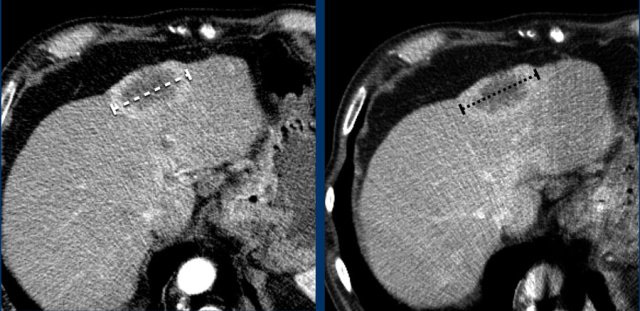

Measurement includes hypervascular rim

When a lesion has a hypervascular rim, this is included in measuring the longest diameter, because it represent viable tumor tissue.

The CT images in the arterial and portovenous phase of a 71-year-old male show liver metastases of a neuro-endocrine tumour of the esophagus.

Note that the hypervascular rim is better appreciated in the arterial phase.

The large hypervascular rim is included in the measurement of the largest diameter.